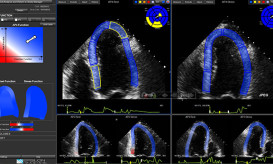

Αποτελεσματικότερη διεύρυνση των παραμέτρων που χρησιμοποιούνται συνήθως για να αποκλειστεί ή επιβεβαιωθεί η ισχαιμία και η στεφανιαία νόσος, αλλά...